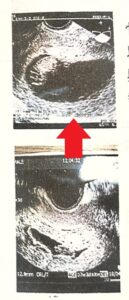

左は前回流産時の子宮内の胎嚢画像。 施術しながら体外受精で妊娠し、右は、出産時の10週時の子宮内の胎嚢画像。

無事に妊娠したものの、出血もあり、不安定で1か月ほど入院していました。 退院後、来院されました。

子宮内の胎嚢の形状が尖っているのと、骨盤のゆるみは5センチ以上ありました。 子宮内の胎嚢の形状が尖っていると流産しやすいという見解を持つ産婦人科医もいます。 ※必ずしも子宮内の胎嚢の形状が丸く改善しないと流産するわけではありません。

そこで、トコちゃんベルト正しい着用を勧めました。 1週間後来院すると、骨盤のゆるみが2センチに改善していました。 無事出産報告がありました。

正しく着用しないと逆に骨盤のゆるみが悪化し、症状の悪化になります。正しく着用して下さい。 |